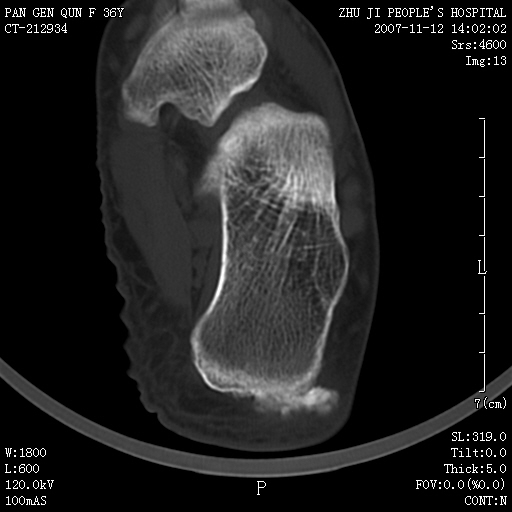

标题: CT10417:F36Y,跟骨跟腱附着处下方骨质密度影,请会诊. [打印本页]

标题: CT10417:F36Y,跟骨跟腱附着处下方骨质密度影,请会诊.

跟骨结节后部肿块半年,无明确外伤史,及红肿热痛.

肌腱骨化

附丽病

附丽病:是指肌腱、关节囊、韧带于骨附着处的骨化和骨质侵蚀改变,常见于坐骨结节、髂骨嵴、坐骨耻骨支、股骨大小粗隆、跟骨结节等处。

x线表现为具有骨密度的细条索状影自骨面伸向附近的韧带、肌腱,宛如浓厚的胡须,以病变晚期更为明显,并有局部骨质侵蚀。